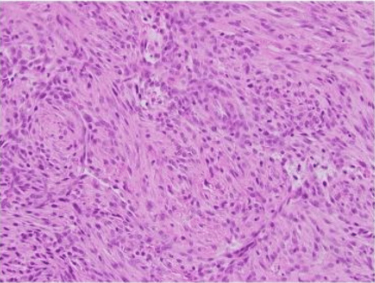

A 3 mm punch biopsy of the lesion was performed. Histopathologic examination revealed nodular collections of histiocytes in the reticular dermis, extending to the specimen’s edges. Many of the histiocytes displayed foamy cytoplasm within a fibrotic stroma, with a rare multinucleated histiocyte present. No mitotic figures were identified. Immunostains for S100, EMA, and CK8/18 were negative, and the Fite stain was also negative.